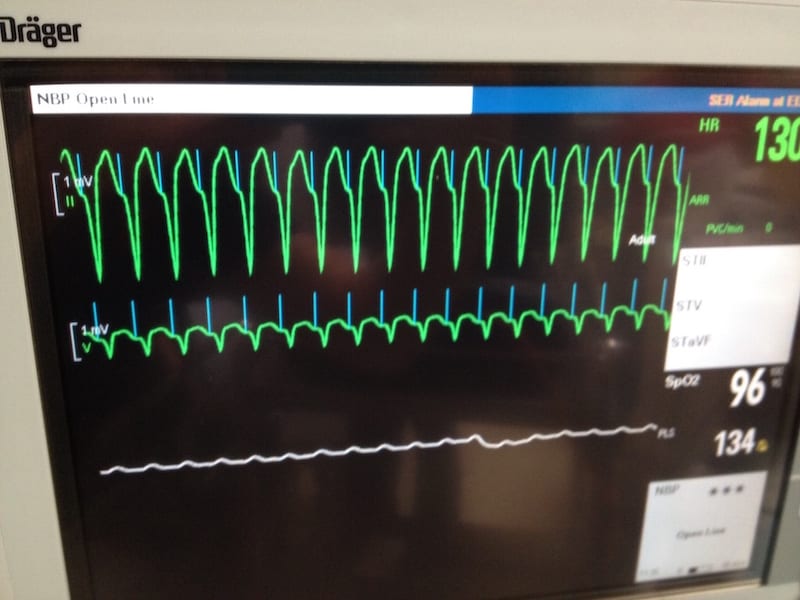

- Broad complex tachycardia at ~ 120 bpm.

- Pacing spikes precede each QRS complex.

- LBBB morphology (dominant S wave in V1-2) indicates a pacing electrode in the right ventricle.

- Negative concordance is seen in V1-6 (all precordial leads

show negative complexes). This is an often-cited feature of VT, but also

occurs with paced rhythms. It simply indicates that ventricular

depolarisation is spreading from anterior to posterior (away from V1-6),

e.g. due to a pacemaker electrode stimulating the anterior wall of the

RV.

These features are consistent with a pacemaker malfunction resulting in a rapid ventricular-paced rhythm.